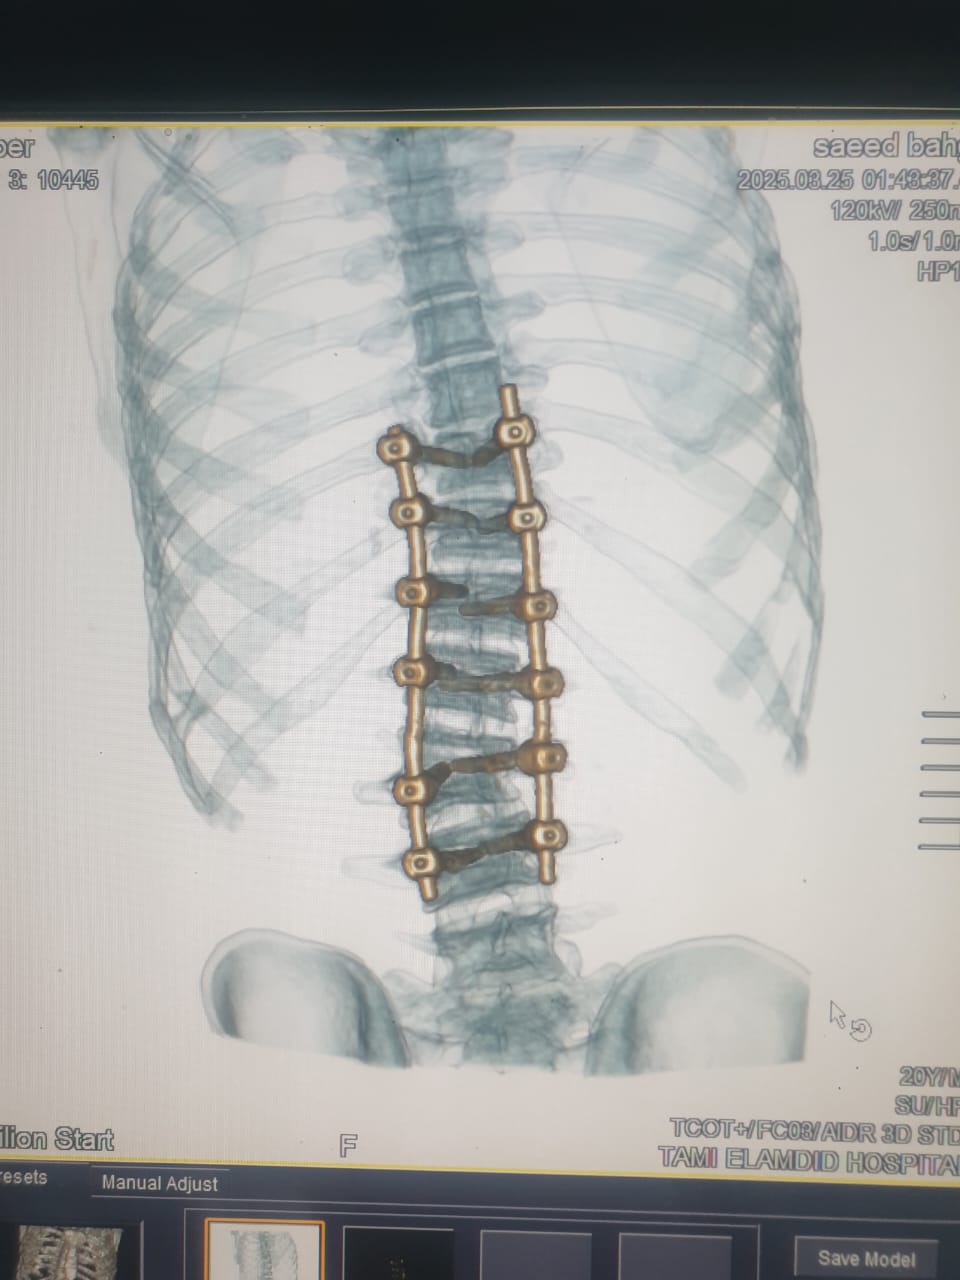

وأضاف مدكور أنه جرى استقبال المريض وهو يعانى من الالام شديدة بالظهر مع عدم الاستجابه للعلاج الدوائي والعلاج الطبيعى وعقب الفحص تبين وجود اعوجاج بالفقرات الصدريه والقطنيه بالعمود الفقري.

فيما أوضح الدكتور احمد البيلى وكيل المديرية للطب العلاجى أنه عقب مناظرة الاشعة والفحوصات تم إجراء العملية التى استغرقت 4 ساعات كاملة لإصلاح الاعوجاج بواسطه تثبيت الفقرات الصدريه والقطنيه واستعدال العمود الفقرى مع خروج المريض من المستشفى وتحسن حالته.